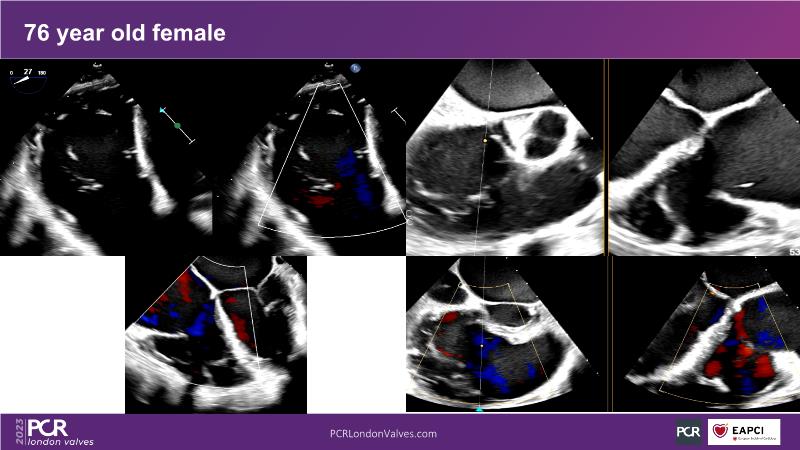

- To learn about the differentiating features of the PASCAL Precision system showcased in a series of simulators alongside case presentations

- To interact with a panel of experts discussing the PASCAL Precision system technology and showcasing, live, its different key features in action and how they help treat mitral regurgitation and tricuspid regurgitation patients